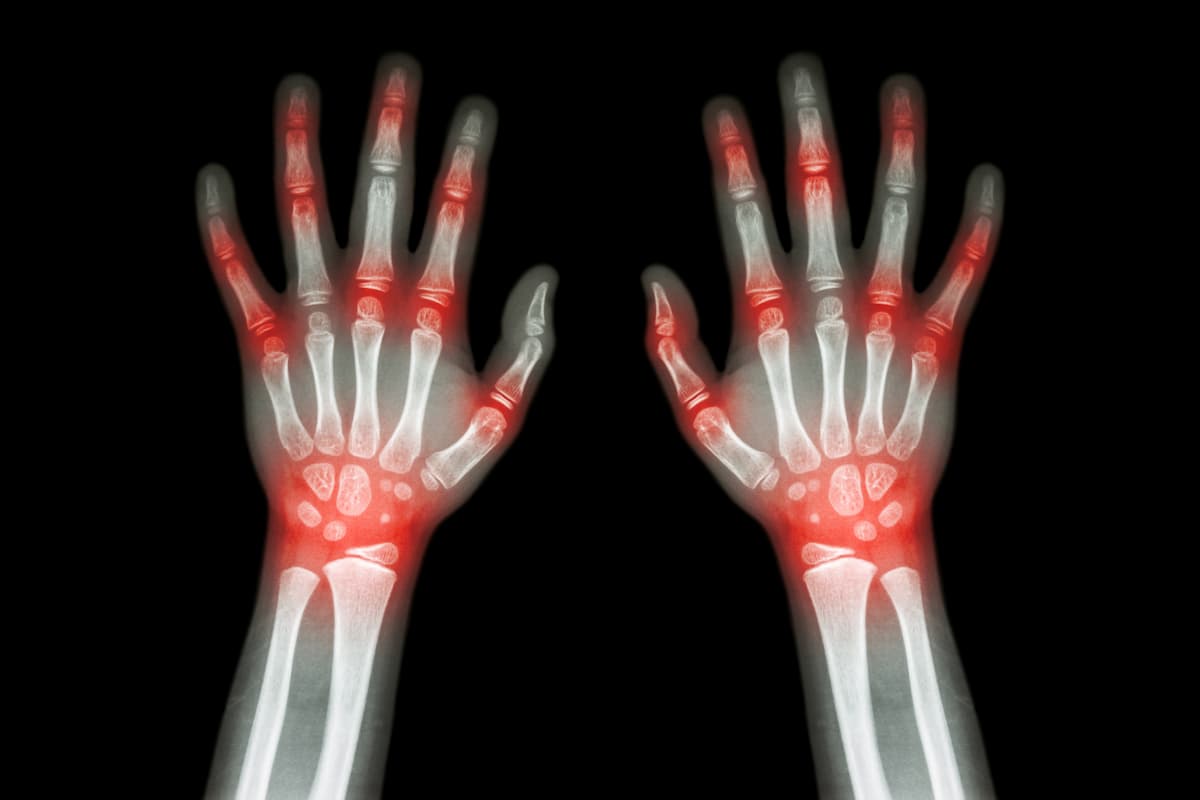

Investigators explored biological and non-biological factors, including psychological and socioeconomic factors, linked to pactiveRA | Image credit: stockdevil - stock.adobe.com

To determine which biological and non-biological, including psychological and socioeconomic, factors were linked to pactiveRA, investigators assessed adult patients with early RA living in England who were included in the National Early Inflammatory Arthritis Audit database from May 2018 to October 2022 in.